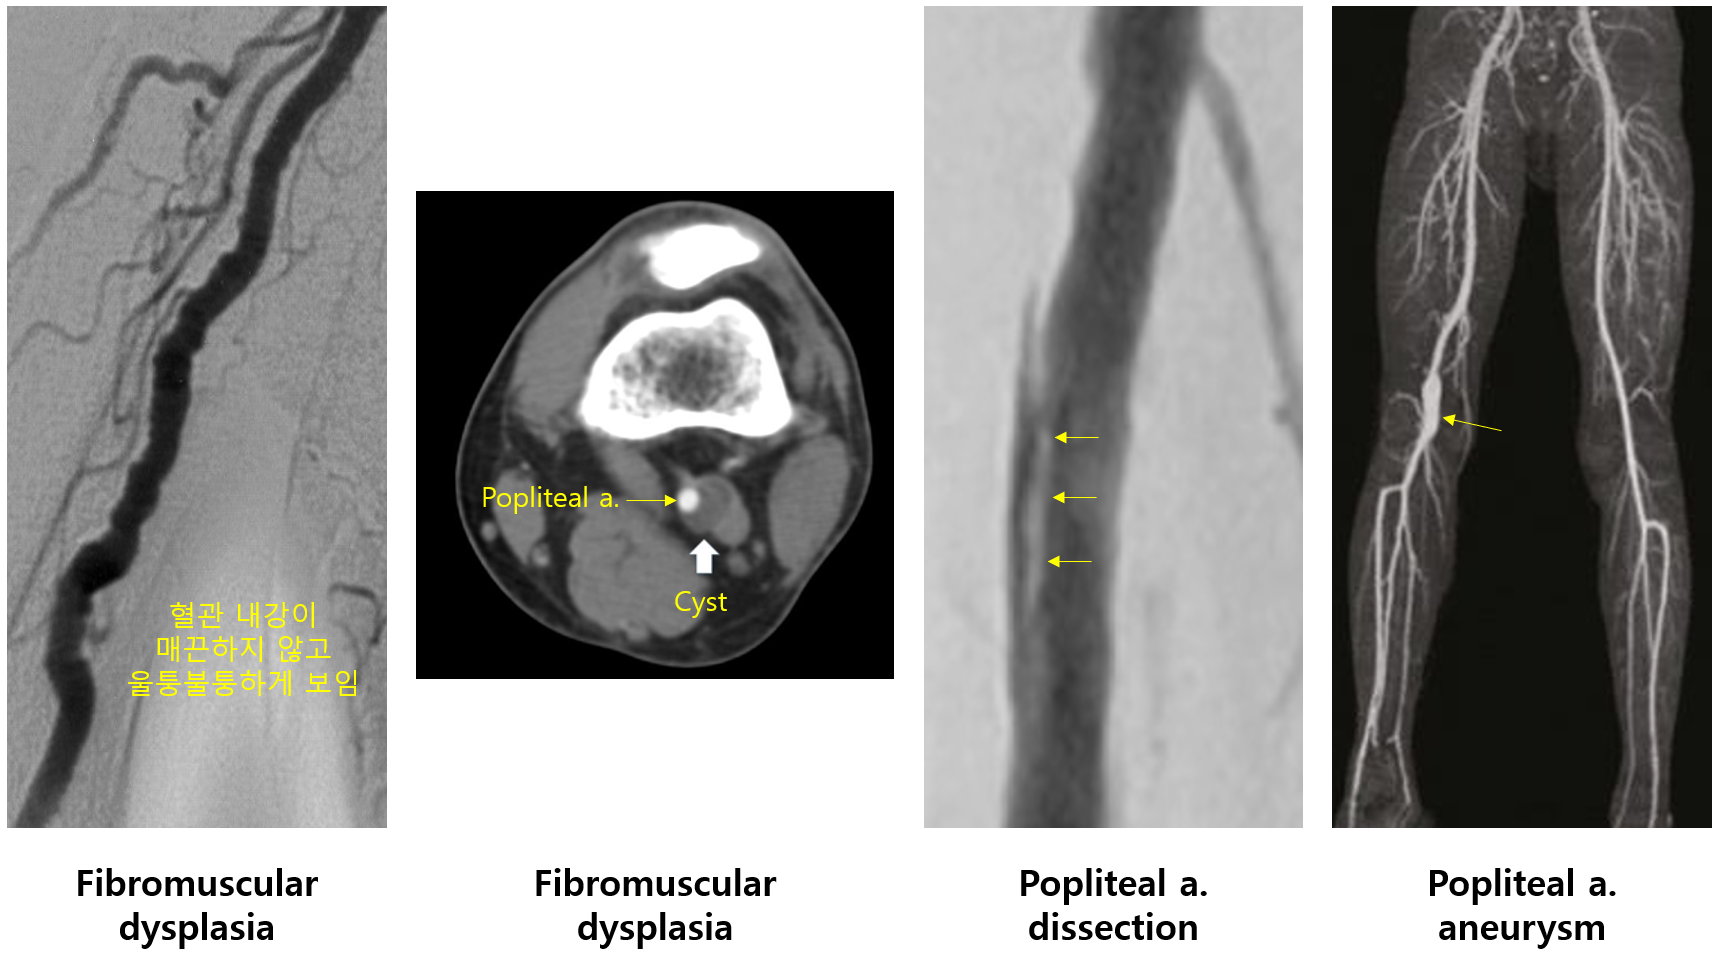

2) 섬유근육 형성이상(fibromuscular dysplasia)

(1) 혈관 조직의 hyperplasia/dysplasia로 인해 혈관 내강이 좁아지는 질환

(2) 진단: Angiography - 'string of beads' apperance

(3) 치료: 혈관내 시술, 수술

3) 낭포성 외막질환(cystic adventitial disease)

(1) 혈관의 adventitia에 cyst가 자라면서 혈관 내강이 좁아지는 질환

(2) 진단: Angiography (특히 angiography가 유용)

(3) 치료: 수술적 제거

4) 기타: Popliteal artery dissection, aneurysm